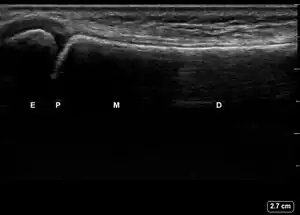

| 1 | Angulation of the distal bone segment[14] | ![]() Ultrasound view of angulation of distal bone segment (shown by arrow). E = epiphysis; P = physis; M = metaphysis; D = diaphysis. | |

| 2 | Fracture < 1 cm from physis | ![]() Ultrasound view of buckle fracture < 1 cm from physis (shown by arrow). E = epiphysis; P = physis; M = metaphysis; D = diaphysis. | |